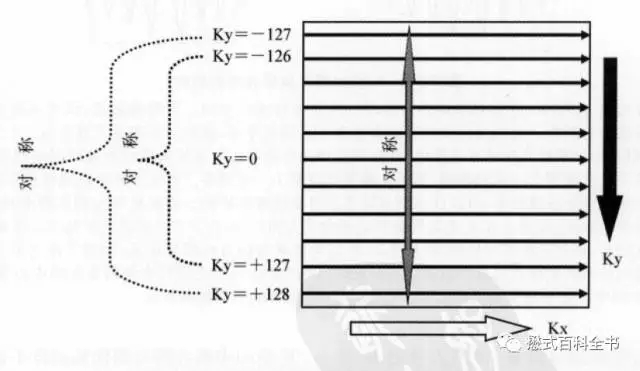

相位编码方向也是对称的。因为每次相位编码梯度会变化,在K空间中心的时候,不施加相位编码梯度(相位编码梯度为0),在两边分别依次递增相位编码梯度,但是两边的方向相反,所以在相位编方向,K空间也是对称的。

图10:相位编码方向上K空间的对称性